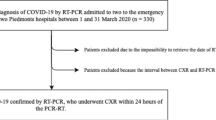

From 1 to 22 March of 2020, patients who (1) presented with pneumonia symptoms (two or more of the following: T ≥ 37.5 °C, cough, dyspnea), (2) had a positive lung CT scan, and (3) had confirmed SARS-CoV-2 infection on RT-PCR were consecutively enrolled. The timespan of enrollment coincided with the ascending phase of the pandemic in our region. We excluded patients with significant motion artifacts on CT scan, i.e., respiratory artifacts that were present in the pulmonary bases plus other lung zones. A flow chart diagram is shown in Fig. 1.